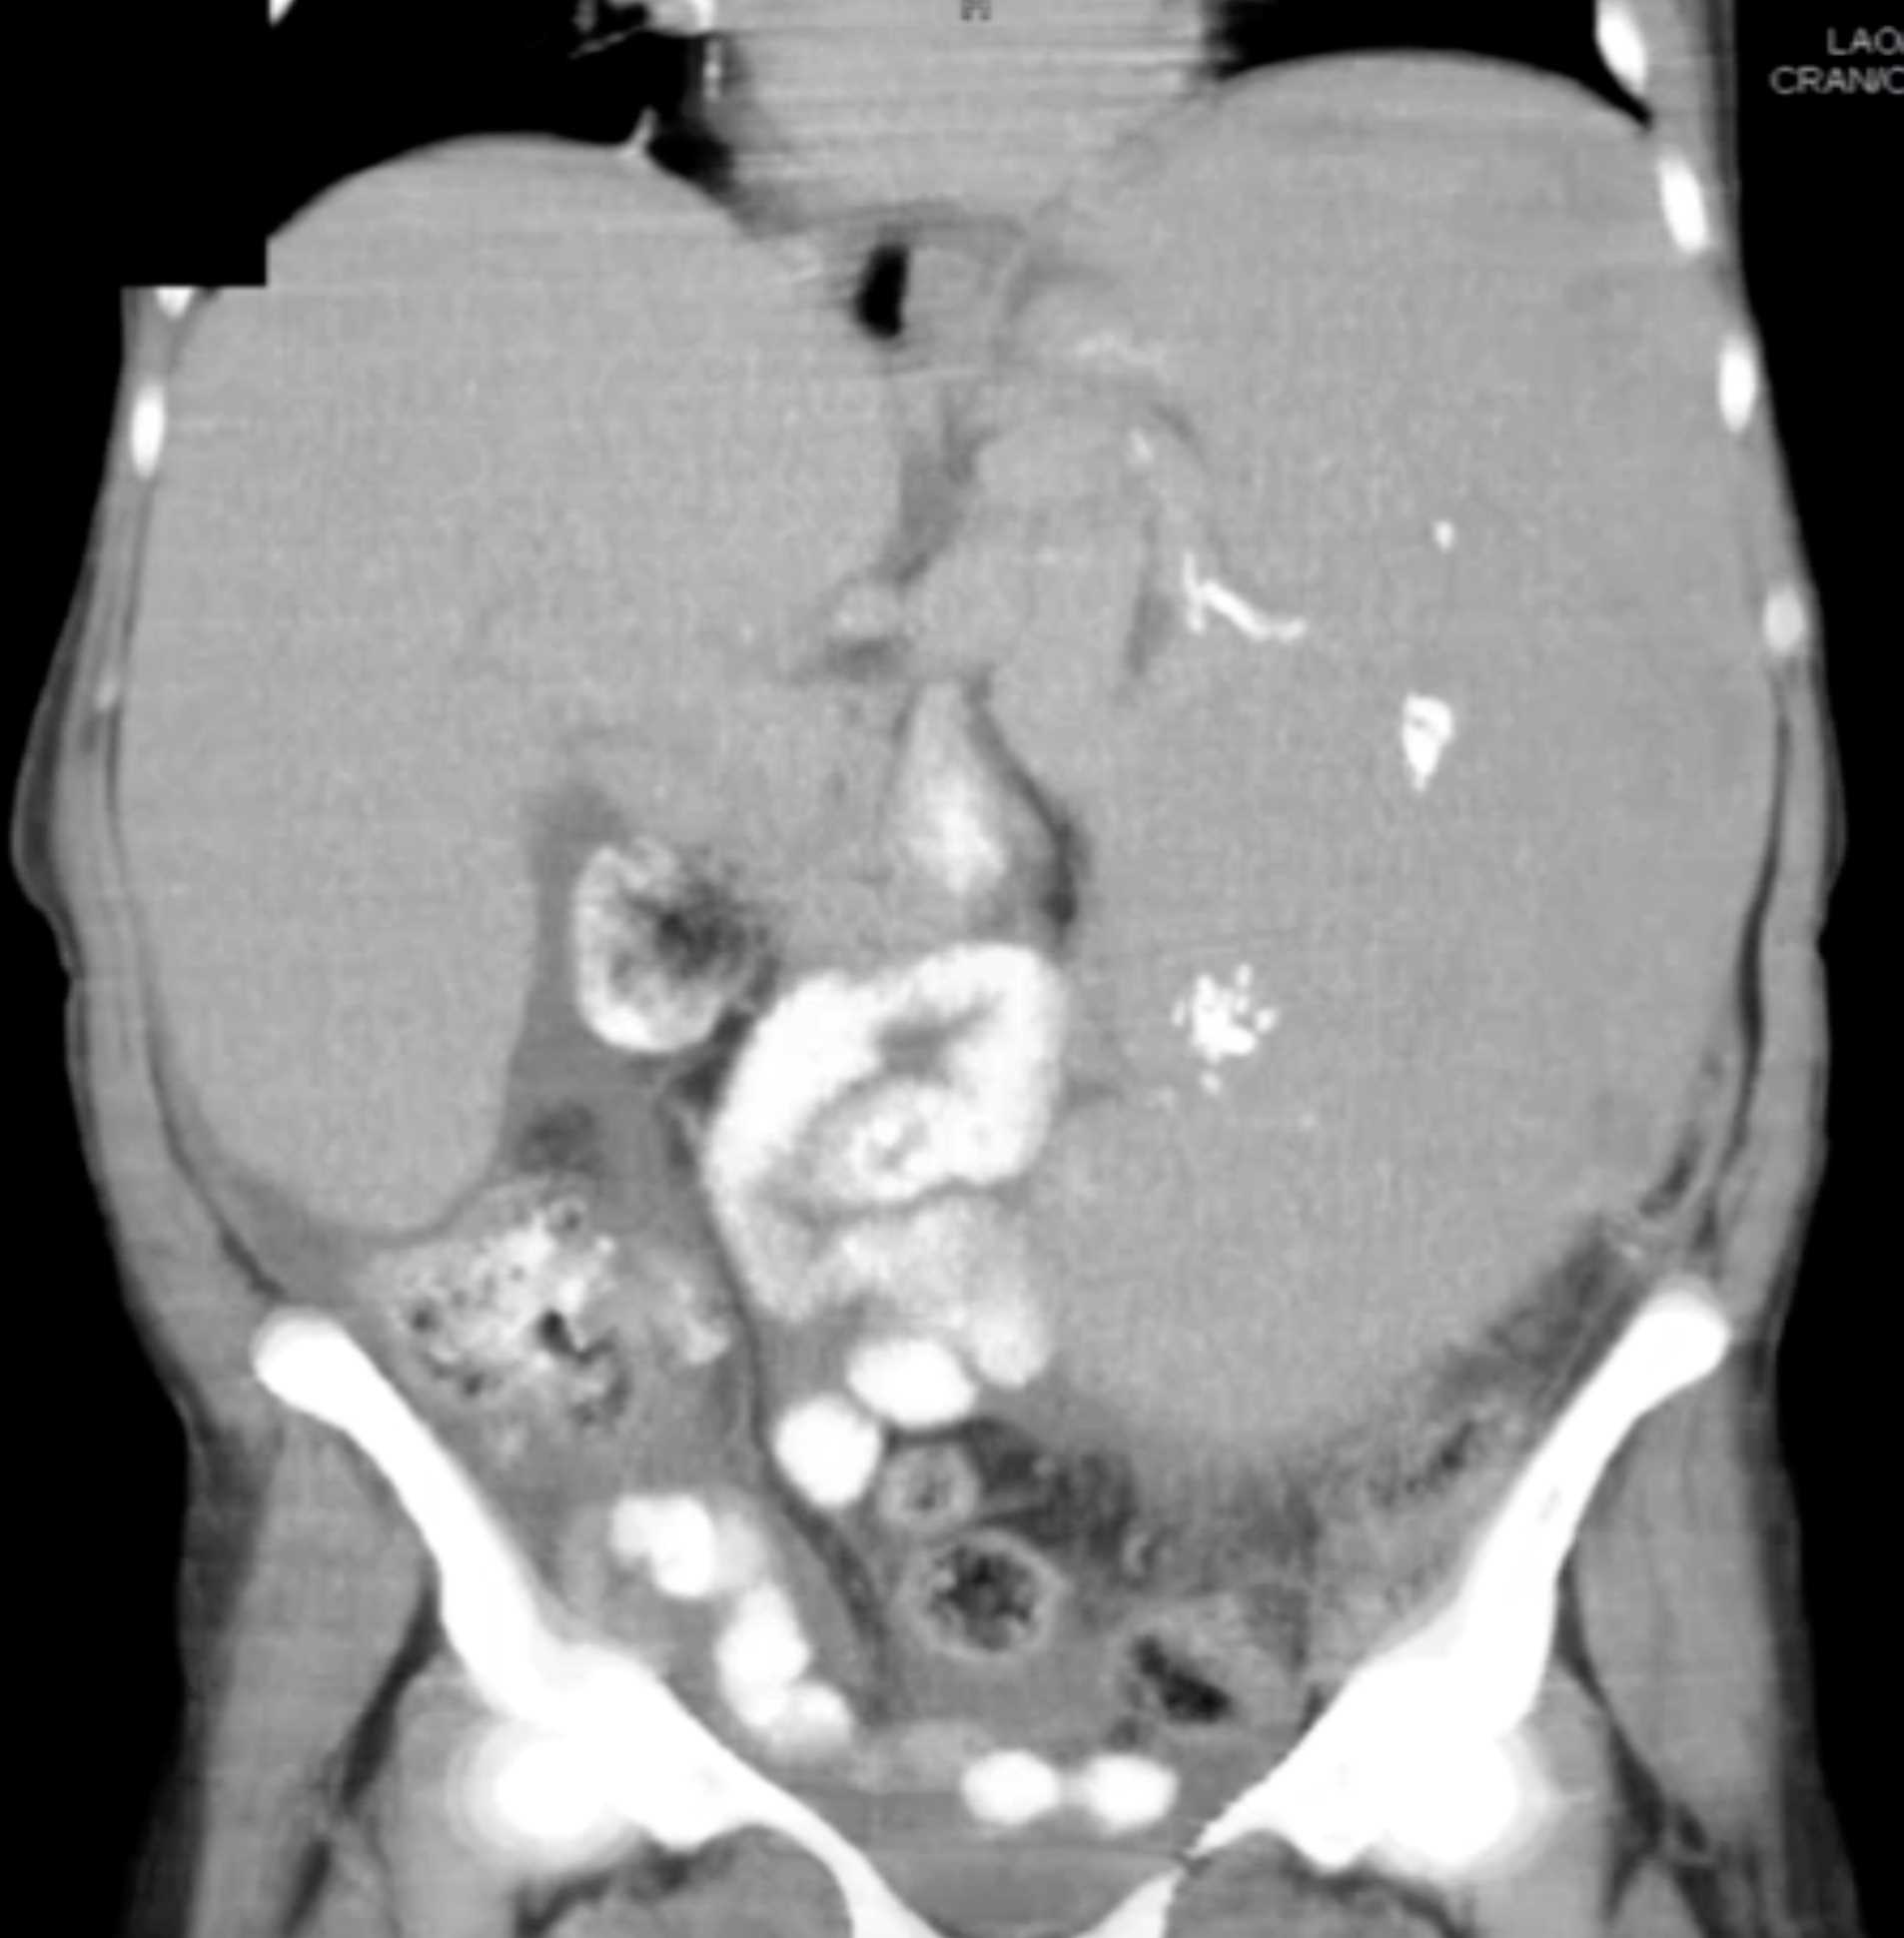

Gaucher's Spleen